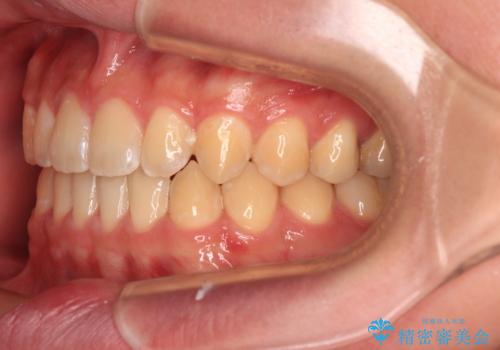

舌の突出癖がなかなか改善されず、治療期間は当初予定よりも大分長くなりました。

装置除去を予定していた日に、油断されたのか1mmほどのスペースを作ってしまったため、除去が3ヶ月延長されたことで、舌のトレーニングの重要性を理解していただきました。

装置除去後もトレーニングを継続されているようで、後戻りによるスペースは今のところ認められておりません。